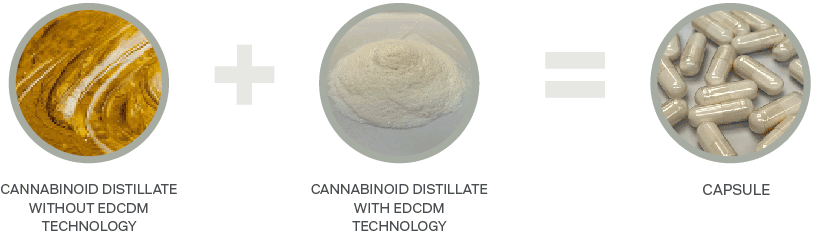

Enhanced Distillate Capture and Dissolution Matrix (EDCDM) technology

Zelira has successfully developed and demonstrated enhanced dissolution of cannabinoids using its enhanced distillate capture and dissolution matrix (EDCDM)

Before this breakthrough technology was developed by Zelira cannabis manufacturers had difficulty in formulating and developing free flow solid oral dosage forms based on cannabinoid distillate. This is due to the non-uniformity of cannabinoid distillate and its separation from the powder bed. EDCDM technology, developed by Zelira, resolves this problem by creating the capacity to capture distillate in a unique and proprietary matrix. When combined with the cannabinoid distillate, it creates a free-flowing powder base for capsules and tablets.

Enhanced Distillate Capture and Dissolution Matrix (EDCDM)

This novel matrix absorbs the distillate into a nano porous silicate particle where the distillate is effectively trapped in the structure of the silicate rendering the powder bed dry. As a result, this prevents the distillate from separating from the powder bed during encapsulation and under the compression forces utilised in tableting thus opening new ways to develop pharmaceutical grade, cannabinoid-based medicines in solid oral dosage forms such as capsules and tablets.